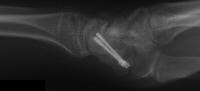

Healed.

The patient requested hardware removal prior to enlisting for military duty. Final films.